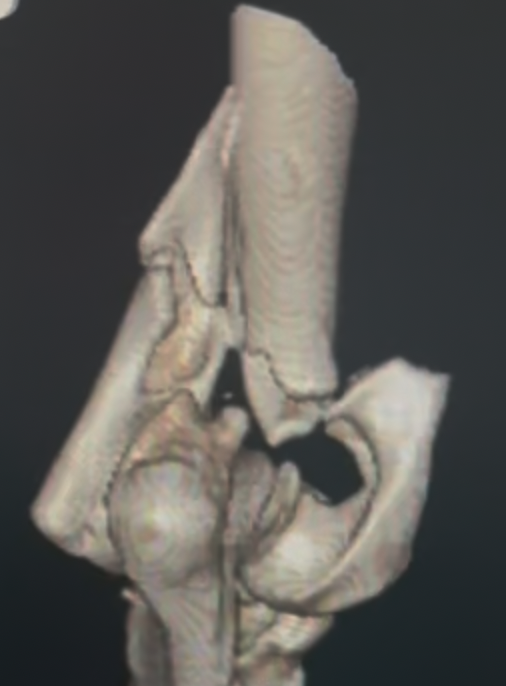

Diagnosis begins with an orthopedic exam. High-quality radiographs are essential. If the fracture is complex — particularly bicondylar fractures or suspected Humeral Intracondylar Fissure (HIF) — a CT scan may be recommended for a more complete view.

Prompt and accurate repair is critical. Surgery typically involves placement of a transcondylar screw to stabilize the fracture, often paired with plates or pins for additional support. Bicondylar fractures are especially challenging because the elbow is effectively split into three pieces, requiring meticulous reconstruction.

Humeral condylar fractures require surgeons with extensive experience and specialized tools. At AOCF, advanced imaging (CT and fluoroscopy) helps us understand the fracture before and during surgery. We maintain a full range of implants for even the most complex repairs and use minimally invasive techniques when appropriate. This approach ensures precise reconstruction, faster recovery, and the best possible long-term outcome for your pet.

Radiographs (X-rays) are the most important initial diagnostic tool. They are taken from multiple angles and often include the opposite limb for comparison. In more complex cases, a CT scan may be performed to create a 3D model of the bones, allowing precise surgical planning. If surgery is anticipated, routine bloodwork and urinalysis are also done to ensure your pet is healthy for anesthesia.

In advanced or highly complex cases, 3D-printed surgical guides and detailed pre-operative computer modeling may be used to plan the correction with extreme accuracy.